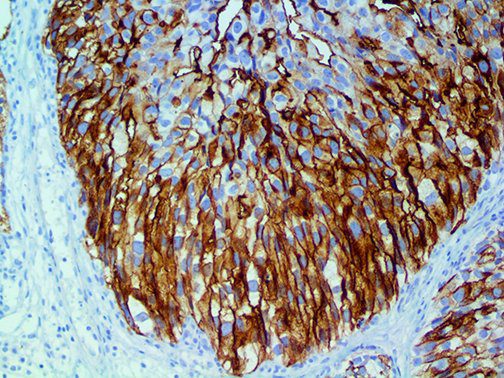

It is the ICU physician who is most likely to witness one of the deadliest manifestations of the abnormal immunological response, the cytokine storm syndrome (CSS). This response is also referred to by some as the cytokine release syndrome (CRS). CSS is characterized by continuous activation and expansion of macrophage and lymphocyte populations, which secrete large amounts of cytokines, causing the cytokine storm. This massive cytokine release is akin to hemophagocytic lymphohistiocytosis (HLH) disease, a syndrome characterized by initial unchecked and persistent activation of cytotoxic T lymphocytes and NK cells.

This activation induces inflammatory monocytes to highly express IL-6, starting a localized and then systemic cascade effect that results in hyperproduction of IL-6, which accelerates the inflammatory process. Because IL-6 also increases vascular permeability, excessive levels cause blood vessels to become very leaky. This, along with clotting factors released from vascular endothelial cells, stimulates the coagulation cascade, resulting in microthrombosis (tiny clots), which leads to ischemia and tissue death of the kidney, intestines, heart, liver, brain and extremities.